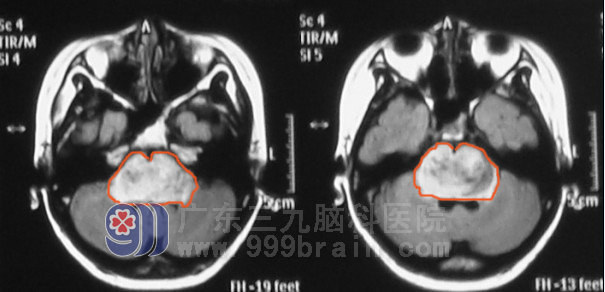

肿瘤综合治疗中心 蔡林波 主任了解小蓉的病情后,发现小蓉不仅行走不稳,还有说话细声且不清晰,检查发现双侧角膜反射消失,双侧咽反射消失。MR显示脑干多处占位,最大占位已经达3*4*4cm,手术难度很大,风险很高。与家属交代病情后,小蓉爸妈很绝望,难道小蓉真的没治了吗?当然不是, 蔡林波 主任告知他们,根据他多年的临床经验和检查结果综合考虑,小蓉应该为脑干胶质瘤,脑干胶质瘤放疗效果很好,特别是现在高水平的适行放疗,它能集中剂量杀灭肿瘤细胞,而且能很好的保护周围组织,对脑干其他正常组织损伤很小,可取得很好的预后。蔡林波主任还给他们介绍了以往许多的类似成功案例。蔡主任细致的讲解让小蓉爸妈重新看到了希望,积极配合医生治疗。在放疗15次后复查头颅MR发现小蓉肿瘤明显缩小,也未再诉头痛,行走较前平稳,继续予行放疗达到合适的剂量。放疗结束后再行六周期辅助化疗,巩固疗效。www.999brain.com

昨日小蓉在爸爸的陪伴下返院复查,肿瘤基本消失,小蓉目前走路已和正常人无异。www.999brain.com

▲治疗前

▲治疗后(肿瘤基本消失)